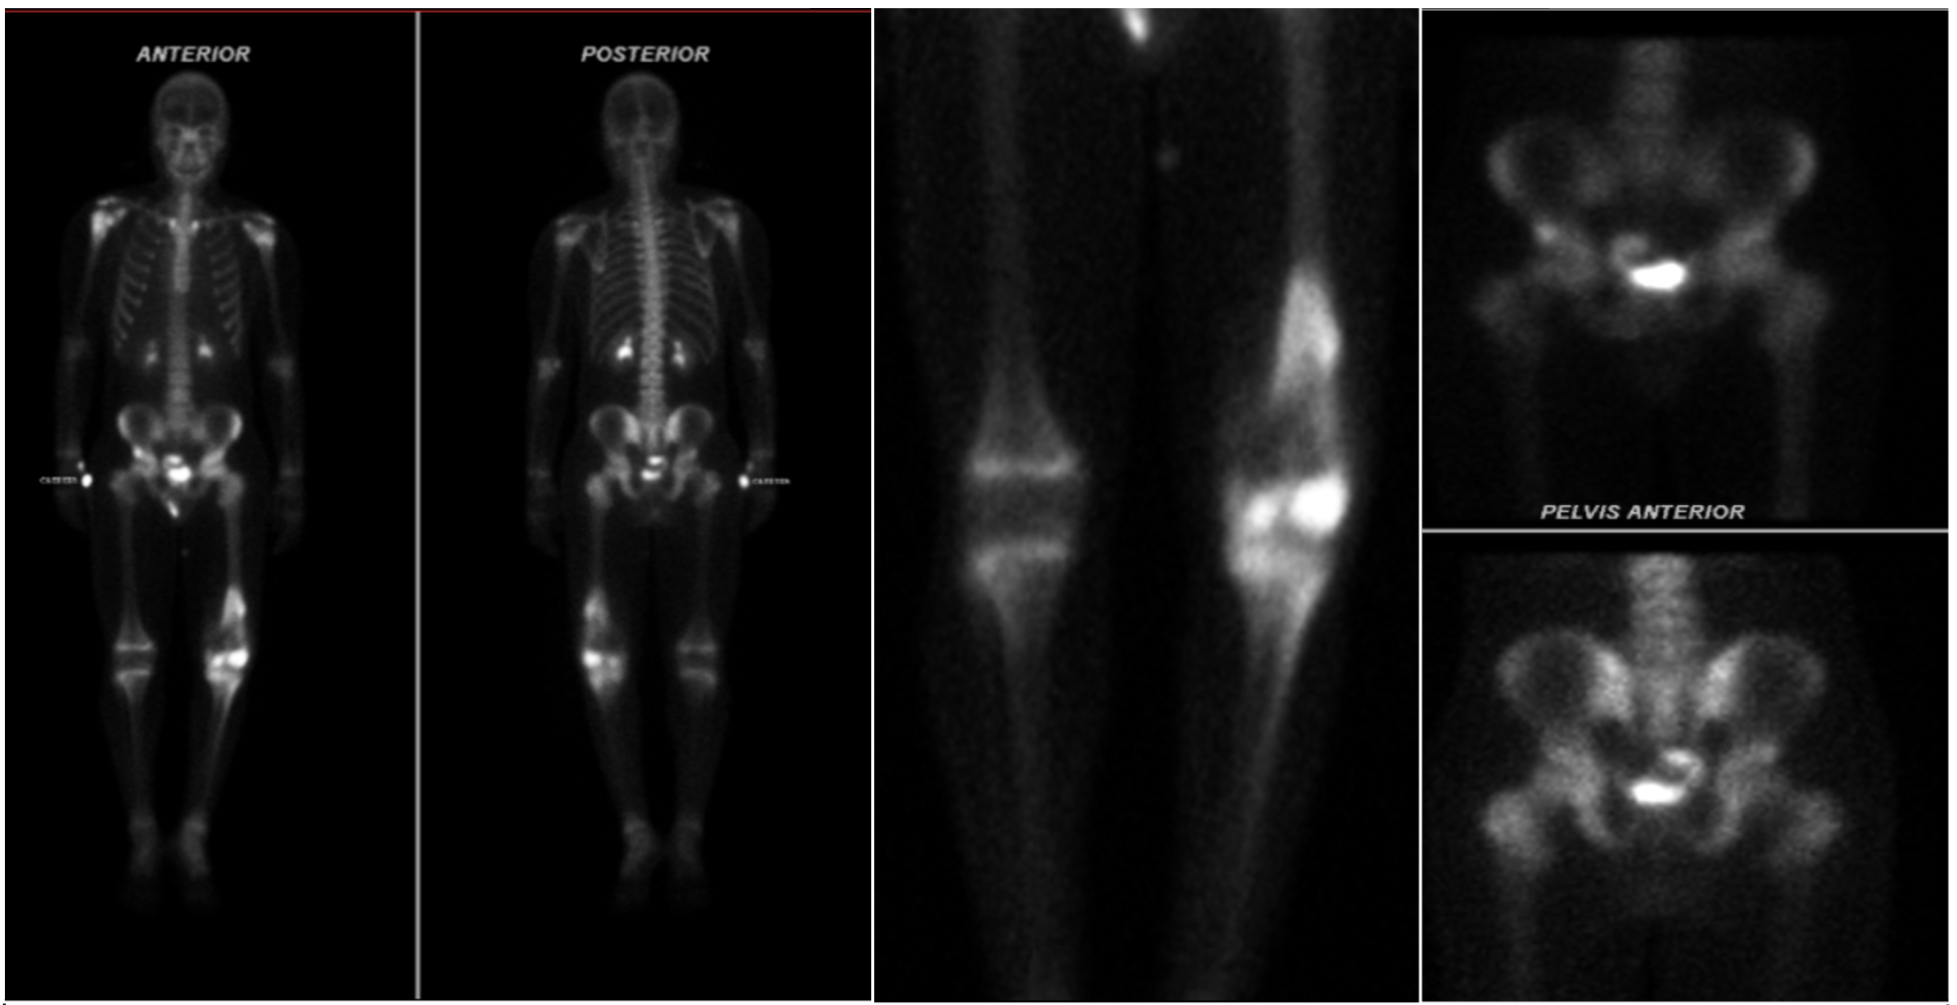

En la radiografía de miembro inferior izquierdo (MII) se aprecia disminución del espacio femorotibial interno con reacción perióstica cortical anterior en tercio distal del fémur y triangulo de Codman (Ver figura 1). En la resonancia magnética nuclear (RMN) de MII con contraste, se observa una lesión de aspecto tumoral a nivel distal del fémur y compromiso del núcleo de crecimiento medial e hidroartrosis (Ver Figura 2). En la gammagrafía ósea se aprecian lesiones blásticas hipercaptantes en diáfisis proximal de humero derecho, espina iliaca anteroinferior, fémur en su diáfisis distal, rotula y tibia izquierda (Ver figura 3). La tomografía axial computarizada (TAC) de tórax y abdomen contrastado fue reportada como normal. El ecocardiograma doppler también fue reportado como normal.

Figura 1. Radiografía de rodillas comparativas.

A. Reacción perióstica cortical anterior en tercio distal de fémur izquierdo y triangulo de Codman. B. Masa pétrea de gran tamaño en tercio distal izquierdo.

Figura 3. Gammagrafía ósea.

Lesiones blásticas con hipercaptación de radiotrazador en diáfisis proximal del húmero derecho, espina iliaca anteroinferior, fémur izquierdo, rotula ipsilateral y tibia izquierda.

Figura 5. Gammagrafía ósea.

Estudio de control con hipercaptación del radioatrazador en, diáfisis proximal de humero derecho, hueso iliaco y acetábulos derechos, además presenta lesiones en fémur izquierdo con área de mayor captación en la diáfisis distal, sin nuevas lesiones en comparación con gammagrafía previa.